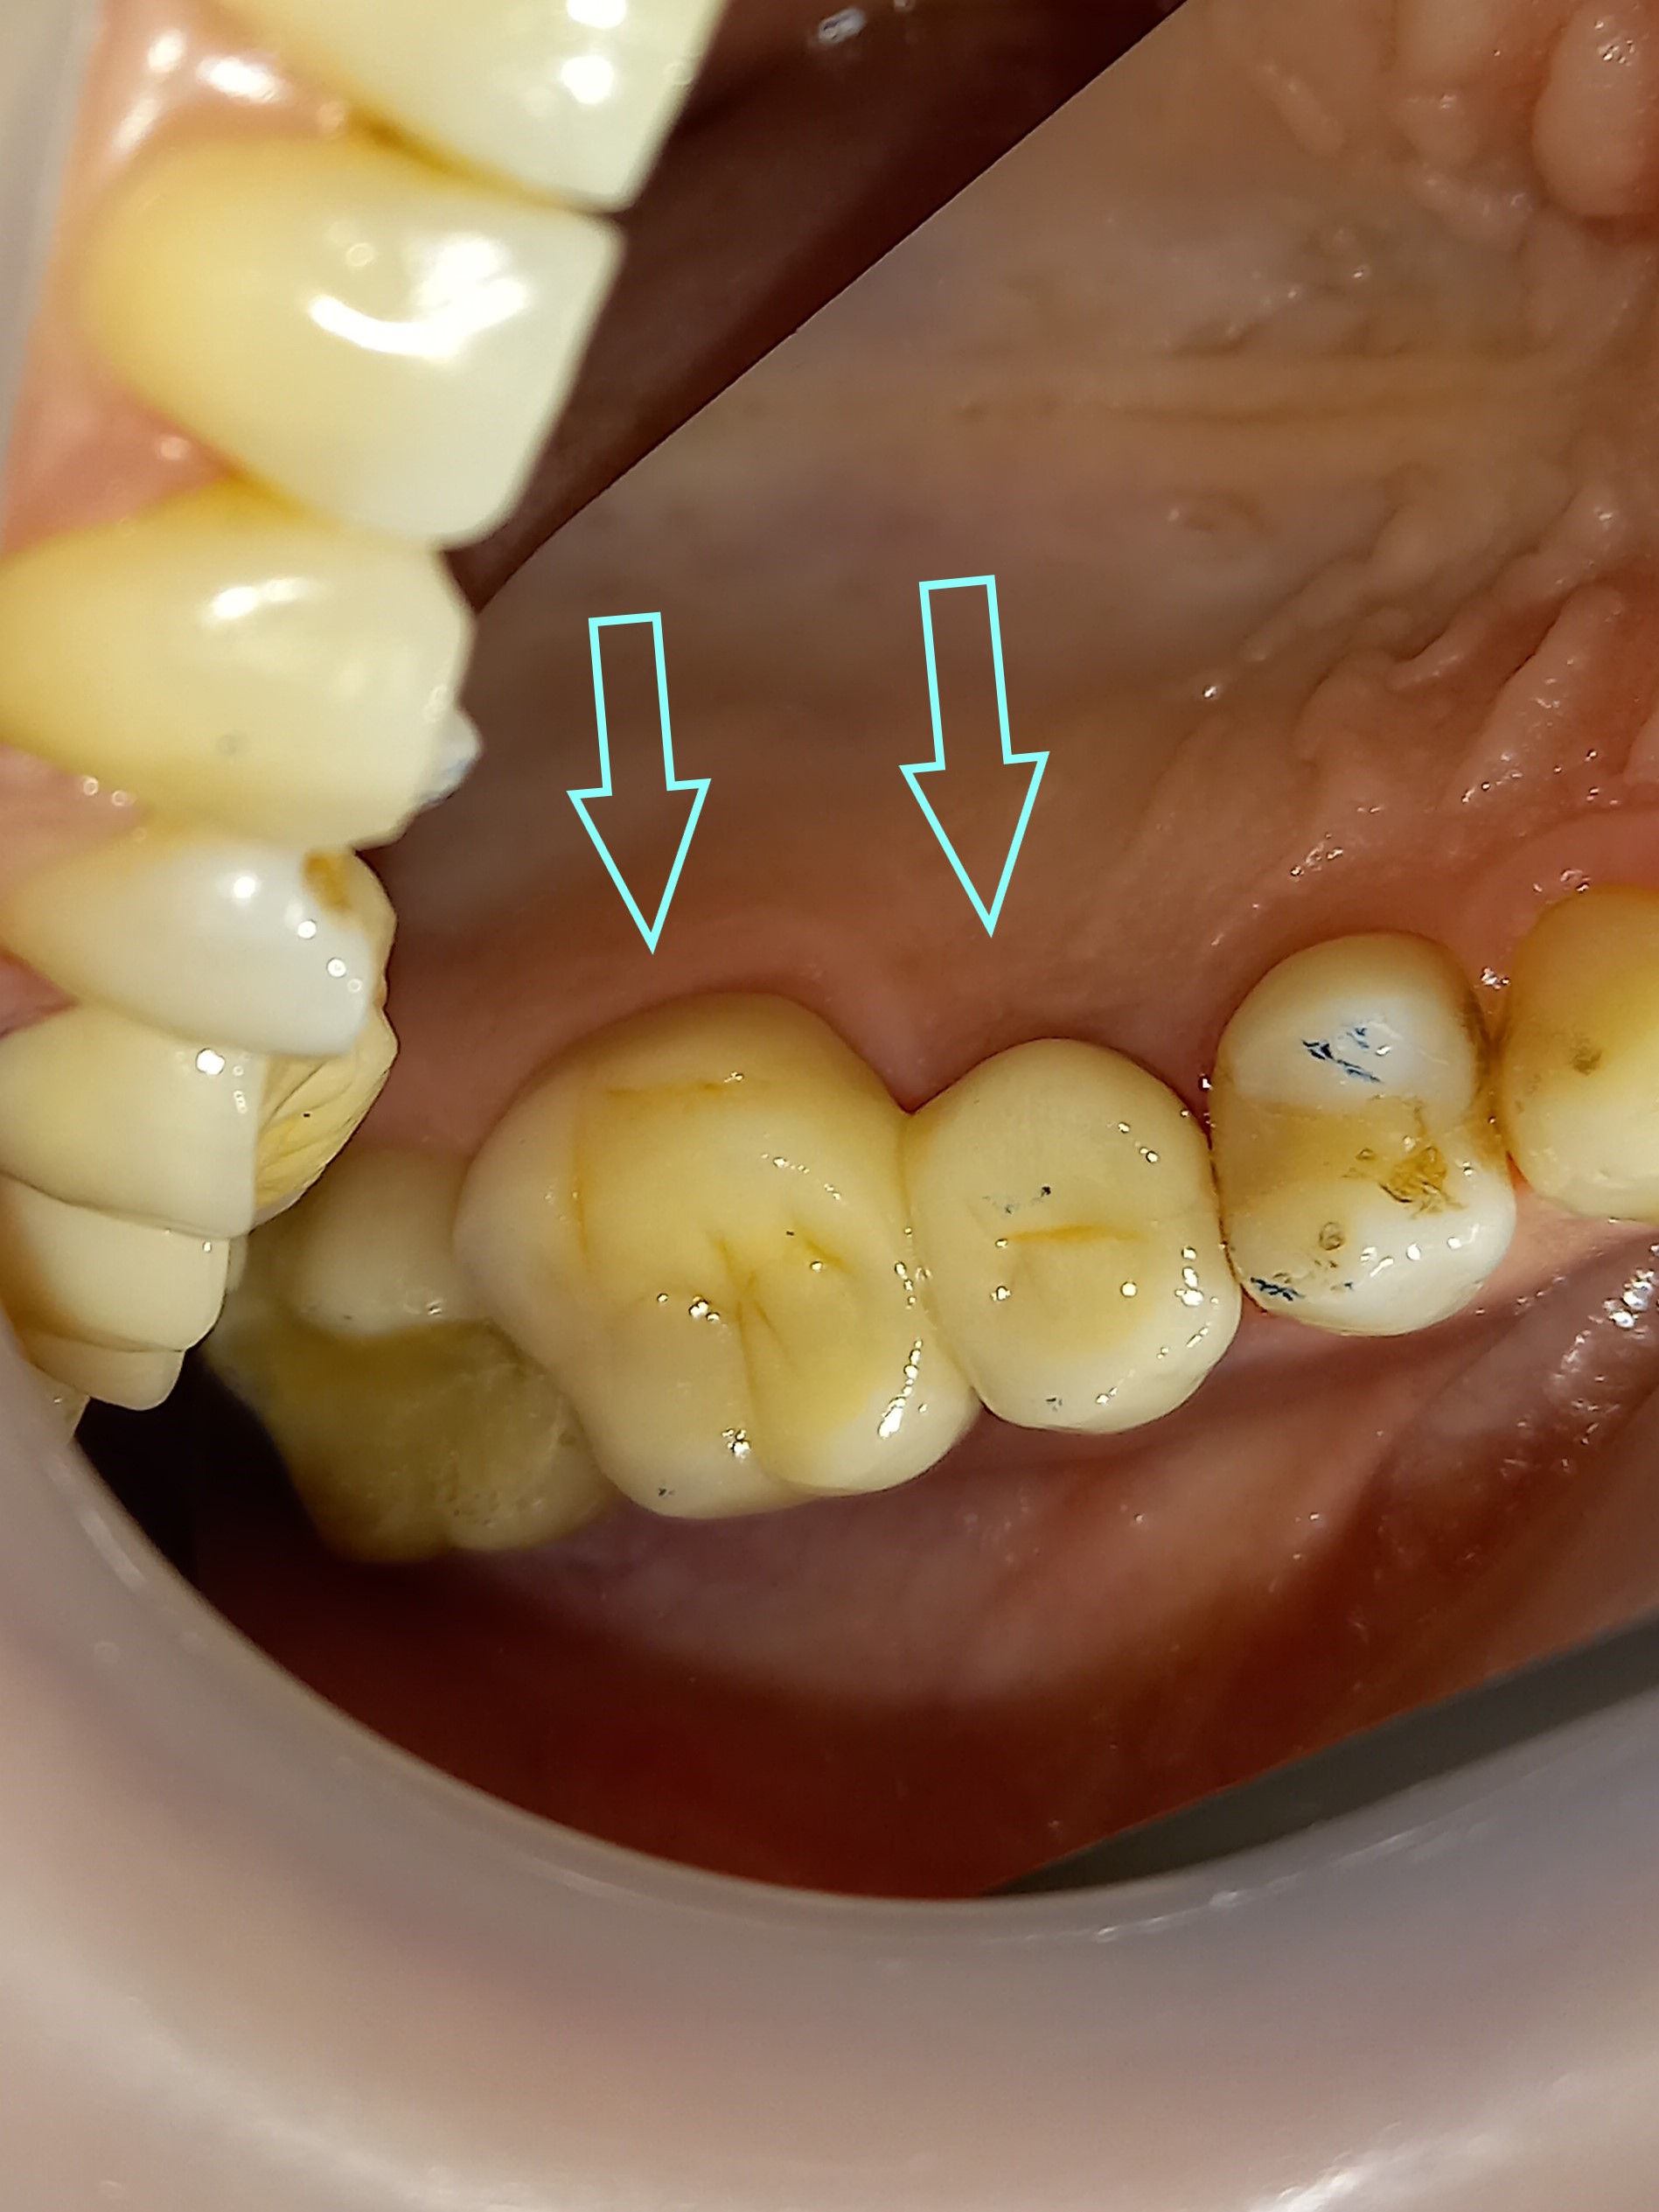

Αρχική κλινική εικόνα του μεγάλου οδοντικού ελλείμματος

Τελική κλινική εικόνα του ολοκεραμικού επένθετου στο γομφίο